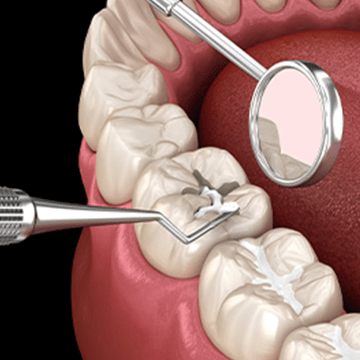

01충치치료

단계별로 치료 방법이 다릅니다.

1 치아표면이 법랑질까지

진행된 경우‘레진 치료’ 가능

2 상아질 경계와 상아질까지

진행된 경우충치 부위를 삭제한 후

삭제 부위에 ‘인레이 치료’ -

03충치치료 방식

치료방식 정확하게 구분하세요.

레진 재료: 레진, 아말감 좁은 충치 부위의 병소를 제거한 뒤

파진 곳을 수복제를 이용하여

채워 넣는 방식입니다.

충치의 범위가 크지 않으며 심하지 않은

충치 치료 시 사용되는 방법입니다. -